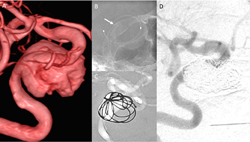

圖二、(A)右側內頸動脈岩部段有一16x20-mm的大型動脈瘤;合併導流裝置;(B)如箭號以及(C)線圈栓塞治療;(D)半年後門診血管攝影追蹤,動脈瘤已完全閉塞